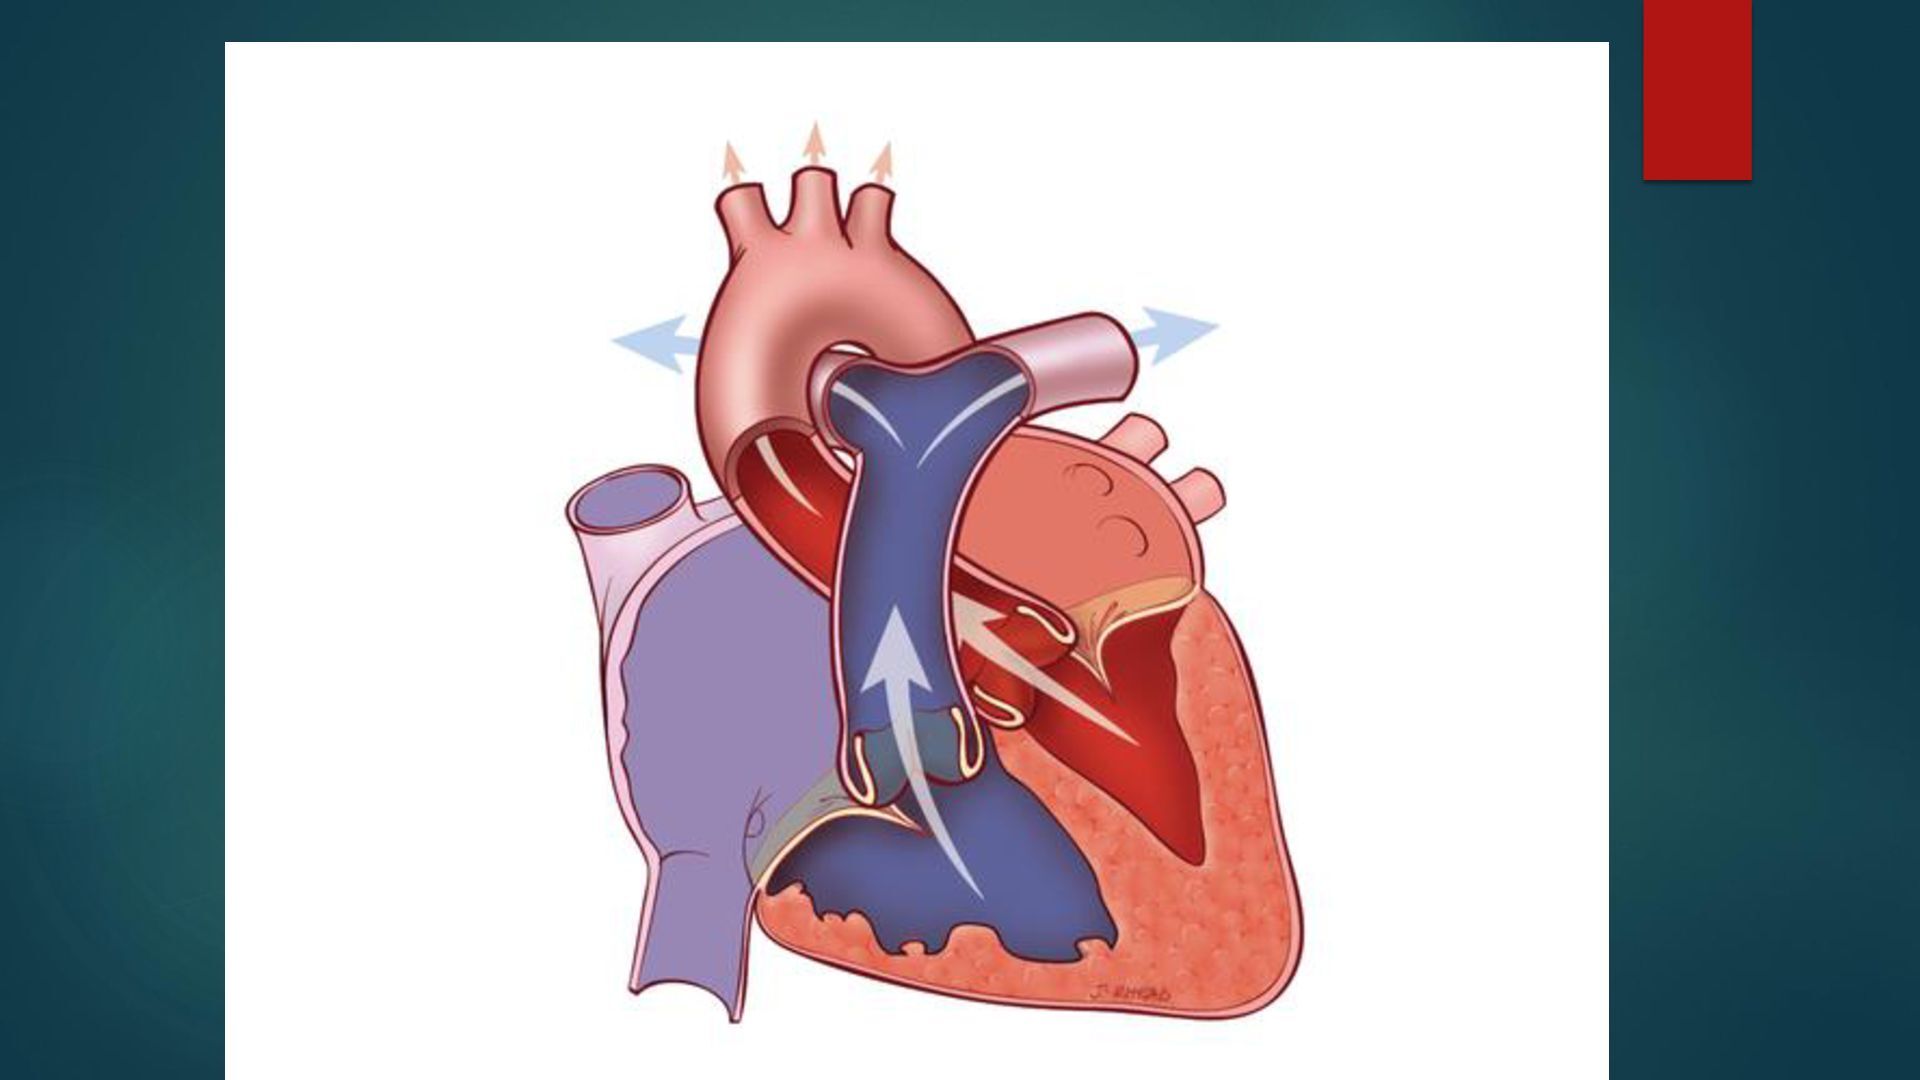

o g a c a r d i o v a s c u l a r ANATOMÍA Y FISIOLOGÍA CARDIOVASCULAR D r a . I s a m a r G . C h a v a r r i a B e r n a r d i n o